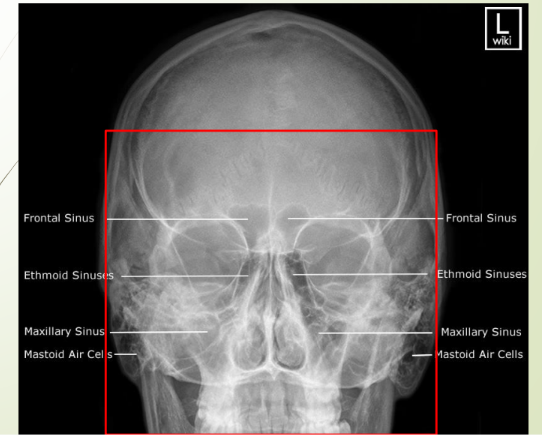

Paranasal sinuses visual

knowt flashcard image